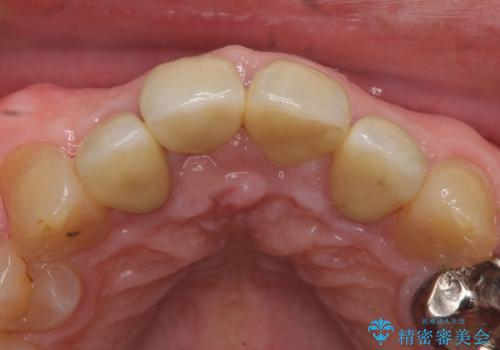

再根管治療後、オールセラミッククラウンによる補綴を行いました。

今回用いたオールセラミッククラウンは、ジルコニアフレームという白い素材の上にセラミックを盛っているため審美性が非常に高いのが特徴です。

またジルコニアは人工ダイヤモンドの材料にも使われているほど高い強度を持っており、そのためオールセラミッククラウンは審美性だけでなく、奥歯やブリッジの補綴も可能とするクラウンです。